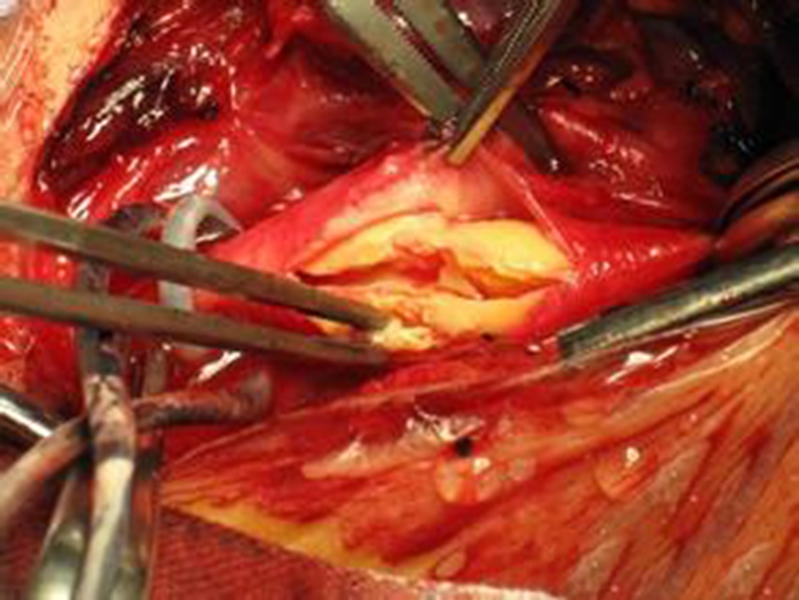

幼兒煙霧病腦手術

幼兒頸部手術煙霧病

幼兒頭部手術煙霧病

煙霧病幼兒頭部

A:煙霧病目前有兩種手術方式,分別是血管搭橋手術和血管貼敷手術。血管搭橋手術是將顳淺動脈進行剝離,然後與大腦中動脈進行吻合搭橋。而血管貼敷手術是將顳淺動脈剝離後貼敷到腦的表面上。通過這兩種手術方式,主要的起到的作用是建立新的側枝循環,從而供應腦……

A:煙霧病的主要手術方式是進行顳淺動脈搭橋手術或者貼敷手術,這種手術是需要進行全身麻醉的,因此做完手術後需要臥床,並且密切觀察病情變化。如果術後恢復順利,那手術後兩三天就可以開始下床活動,早下地能夠起到改善下肢循環的作用,能夠預防出現下肢的深靜……